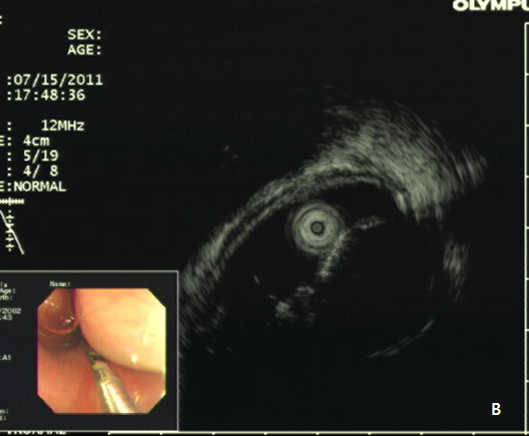

A 42-year -old woman was refferred to our hospital for further evaluation of dysphagia. The patient had no specific past history, and physical examination showed no remarkable findings. Laboratory examination also showed all negative findings. An esophagogastroduodenoscopy (EGD) was performed, and revealed a large, 4 cm sized, elongated SET at upper to mid esophagus, 23~27 cm from incisor (Figure 1A). An endoscopic ultrasonography (EUS) was performed to further evaluate the nature and origin of esophageal SET, which showed a homogenous hypoeshoic mass originated from muscularis propria layer (Figure 1B). We decided to perform endoscopic resection of esophaegeal SET for relief of symptom, and conventional ESD technique was used.2 Briefly, lesion boundaries were identified and marked using argon plasma coagulation connected to an electrosurgical generator (Erbe ICC 200W; Erbe Elektromedizin GmbH, Tübingen, Germany). After injection of a 0.9% saline solution mixed with epinephrine (dilution rate 1:10,000) and indigo carmine dye into the submucosal layer, an initial incision was made 3~5 mm from the regular mucosal layer in a regular interval using needle knife (KD-IL-1, Olympus Optical Co. Ltd.). Submucosal dissection was done with insulated-tipped electrosurgical knife (IT knife) (KD-610L, Olympus Optical Co Ltd.). Dissection of the tumor was performed successfully, however, a large mucosal defect was noted after the procedure (Figure 2A-2D). The resected specimen was 4.2 cm in length and 1.5 cm in diameter, and tumor was diagnosed as leiomyoma by histopathologic examination. The patients had no immediate major complications, and discharged 3 days after the procedure. However, 2 weeks later, the patient complained of significant chest discomfort and dysphagia, and a follow-up EGD showed significant stricture at the procedure site where the scope could not be passed. Endoscopic balloon dilatation was performed and repeated 8 times over 4 months, which led to the resolution of the stricture (Figure 3A-3C).

Figure 1 Esophageal subepithelial tumor (SET).

(A) An esophagogstroduodenoscopy (EGD) showed a large (4.0 cm) SET at upper to mid esophagus. (B) An endoscopic ultrasonography showed a large hypoeshoic mass originated from muscularis propria layer.